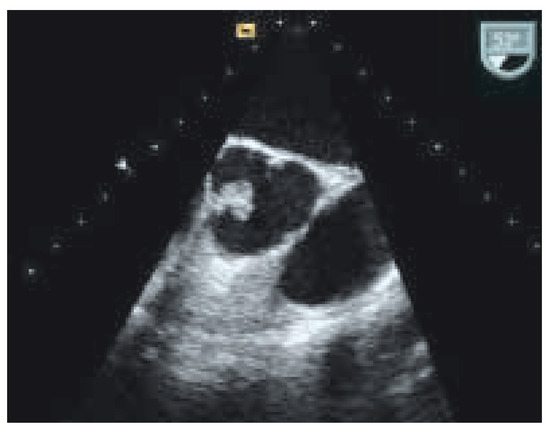

Interesting Images

Kardiales Papilläres Fibroelastom

by Thomas Largiadèr, Michele Genoni and Rolf Jenni

Cardiovasc. Med. 2005, 8(9), 332; https://doi.org/10.4414/cvm.2005.01122 - 30 Sep 2005

Viewed by 142

Abstract

Fallbeschreibung. Eine 73jährige Patientin ohne weitere kardiovaskuläre Risikofaktoren wurde zur Abklärung mit der Fragestellung «kardiale Emboliequelle » nach zerebrovaskulärem Insult mit kompletter Remission zugewiesen [...] Full article

Show Figures

Figure 1